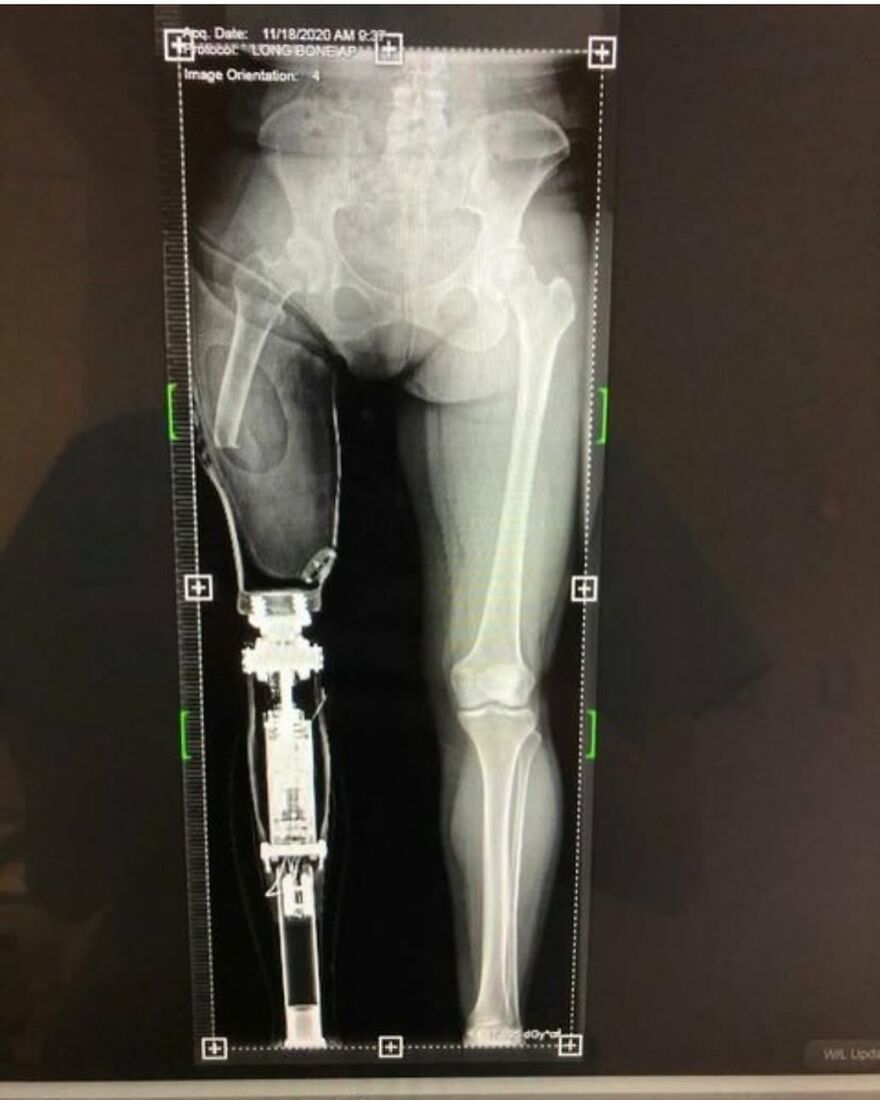

Erm, those last 3 fingers on the left hand side are trying make a run for it!